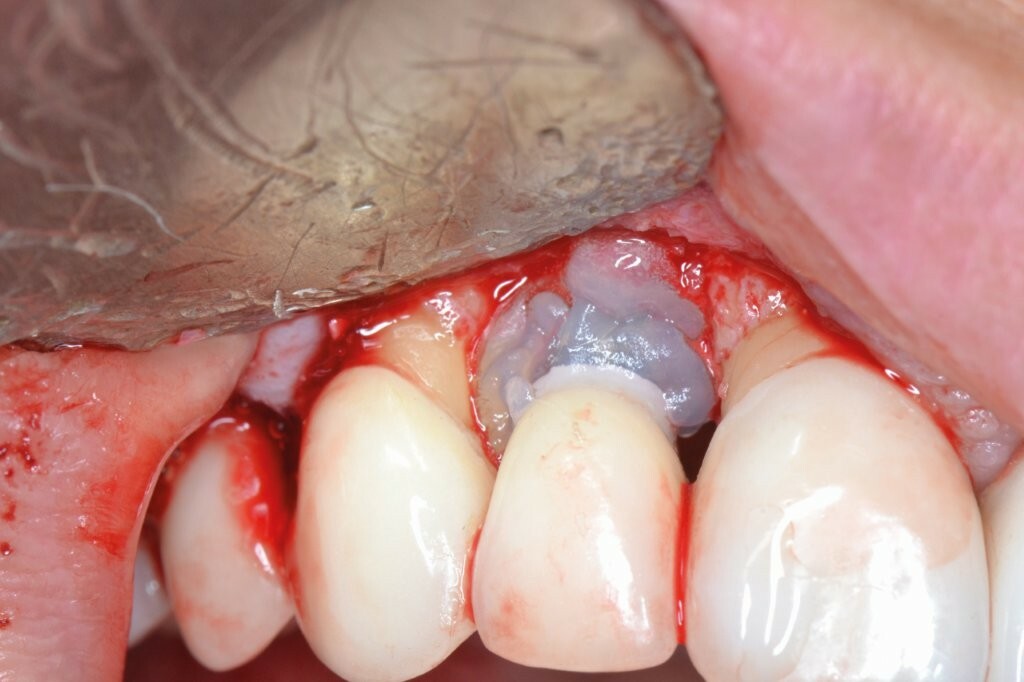

Ein Minilappen wurde sowohl bukkal als auch palatinal am Implantat unter Einbeziehung der beiden Nachbarzähne gebildet. Das entzündete Gewebe wurde kürettiert, wobei wir einen 3 mm großen horizontalen Defekt mit einem stärkeren Knochenverlust auf der bukkalen Seite feststellten. Gemäß des zuvor beschriebenen Protokolls erfolgten zwei aufeinanderfolgende 5-minütige Anwendungen von OXYSAFE-Gel. Der Defekt wurde vorsichtig mit einem Xenotransplantat aufgefüllt und mit einem Kollagenvlies abgedeckt, der Lappen anschließend koronal mit einer Kopfnaht vernäht.